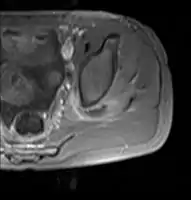

Transverse T2 magnetic resonance imaging section through the hip region showing abscess collection in a patient with pyomyositis.